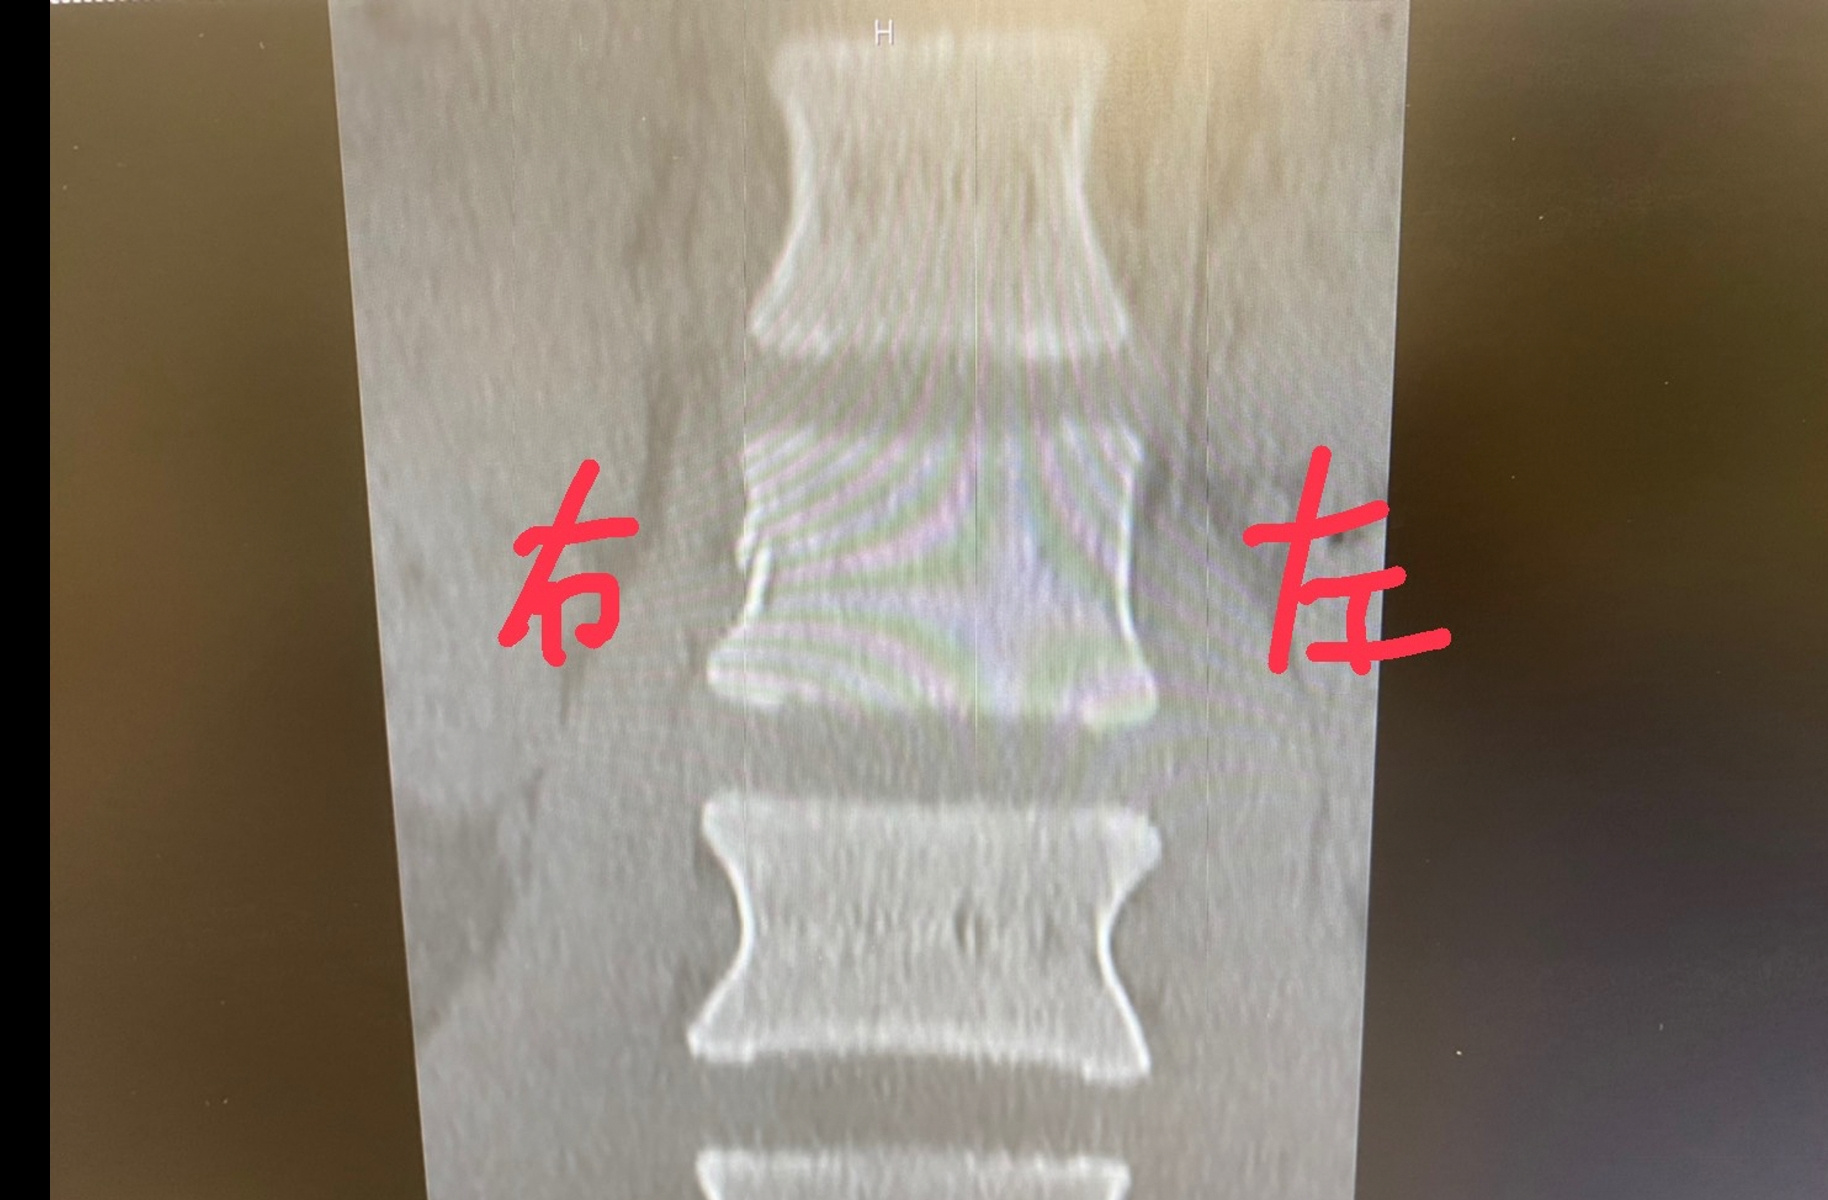

カテゴリー 日常 厚木 投稿者 作成者: Kiyoshi 投稿日 2021/01/28 厚木 へのコメントはまだありません 久しぶりの厚木の工場。 門を開けて入って良いと聞いてたのに 南京錠がかかってて入れず。 7時半頃行くと来たところで すぐに卸してくれた。 スイスの薬局での診断書を作ってもらい 1日早く出られる事になった。 しかし2週間自宅で隔離は変わらず 病院は決められた場所しか行けないらしく 空港近くで診断。 レントゲン。 折れてるのがよくわかる。 ← 東金 → 富士 コメントを残すメールアドレスが公開されることはありません。 * が付いている欄は必須項目ですコメント * 名前 * メール * サイト